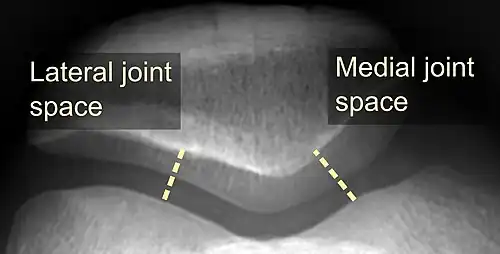

On X-ray, with skyline projections, dislocations are readily diagnosed. In borderline cases of subluxation, the following measurements can be helpful:

- The lateral patellofemoral angle, formed by:[16]

- A line connecting the most anterior points of the medial and lateral facets of the trochlea.

- A tangent to the lateral facet of the patella.

- With the knee in 20° flexed, this angle should normally open laterally.[16]

- The patellofemoral index is the ratio between the thickness of the medial joint space and the lateral joint space (L). With the knee 20° flexed, it should measure 1.6 or less.[16]